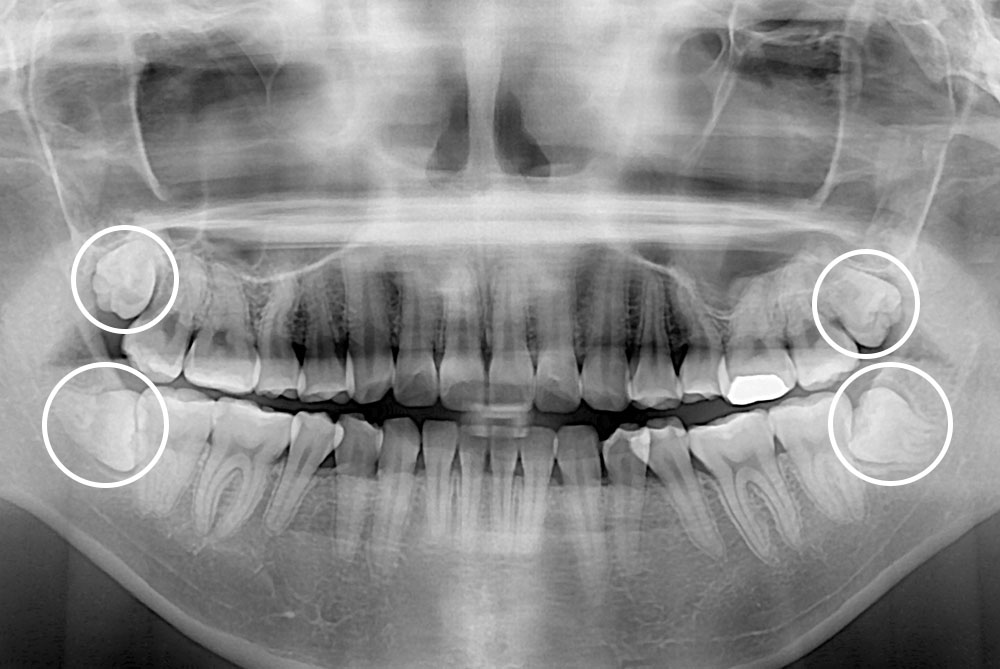

[사랑니] 매복 사랑니 발치

치료후 : 2021-07-05

세종치과는 구강악안면외과학 박사이신 원장님이 발치하는 치과입니다.